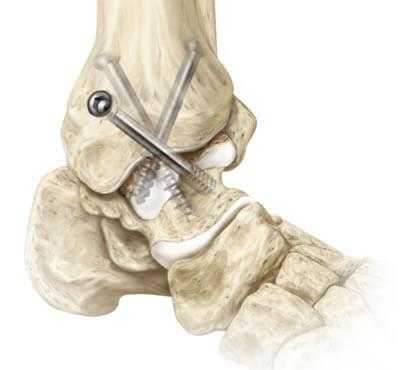

Артродез голеностопного сустава: виды замыкания, показания, осложнения

Артродез голеностопного сустава - оперативное вмешательство по искусственному сращению сочленяющихся суставных поверхностей голеностопа в физиологически выгодном для функционирования ноги положении. Основной целью хирургического лечения является придание опоропрочности проблемной зоне посредством полного блокирования ее подвижности (создания анкилоза). Обездвиживание достигается за счет жесткого соединения примыкающих концов костей сустава между собой специальными фиксаторами из металла (спицами, винтами, штифтами и пр.). Это позволяет прочно срастись суставным поверхностям друг с другом под нужным углом, то есть, привести сочленение в полное неподвижное состояние, что поможет пациенту избавиться от сильной боли и нестабильности стопы.

- Внутрисуставный. В процессе хирургии выполняется вскрытие капсулы сустава с последующим удалением поврежденного гиалинового хряща с поверхностей костных элементов. После репозиции костей в выгодном положении выполняется их фиксация металлическими приспособлениями.

- Внесуставной. Фиксирование костей сочленения только при помощи укладки костного трансплантата, при этом хрящевые покровы резекции не подлежат.

- Комбинированный. Эта техника подразумевает сочетание в одном хирургическом процессе двух способов: внутрисуставного и внесуставного. Так, хрящевые структуры с сустава полностью счищаются, внедряется аутотрансплантат, который фиксируют специальными металлическими пластинами.

- Компрессионный. Операция заключается в сдавливании сочленяющихся поверхностей аппаратом компрессионного или компрессионно-дистракционного типа для дальнейшего их сращения. Широко применяемые конструкции - аппараты Илизарова, Гришина, Волкова-Оганесяна. Удаление хряща не исключается. Вживление костного трансплантата для способа компрессии не требуется.

- На нижнюю треть бедра накладывается пневматический жгут. Далее создают доступ, совершая скальпелем линейный кожный разрез вдоль сустава. Разрез равен примерно 10 см.

- На следующем этапе выполняется вскрытие и надежная супинация сустава, которая облегчит работу с очередными манипуляциями.

- Затем подготавливаются поверхности большеберцовой и таранной костей. Подготовка включает резекцию хрящевых тканей хирургическим долотом, удаление окостенения.

- Дальше стопа выводится из порочного положения. Большеберцовый элемент и таранный компонент плотно сопоставляют друг с другом в удобной с точки зрения физиологии позиции. Достигнутая позиция скрепляется металлической конструкцией необходимого типа.

- Используемые операционные ходы на завершающем этапе закрывают при помощи послойного ушивания мягких тканей с оставлением дренажа.